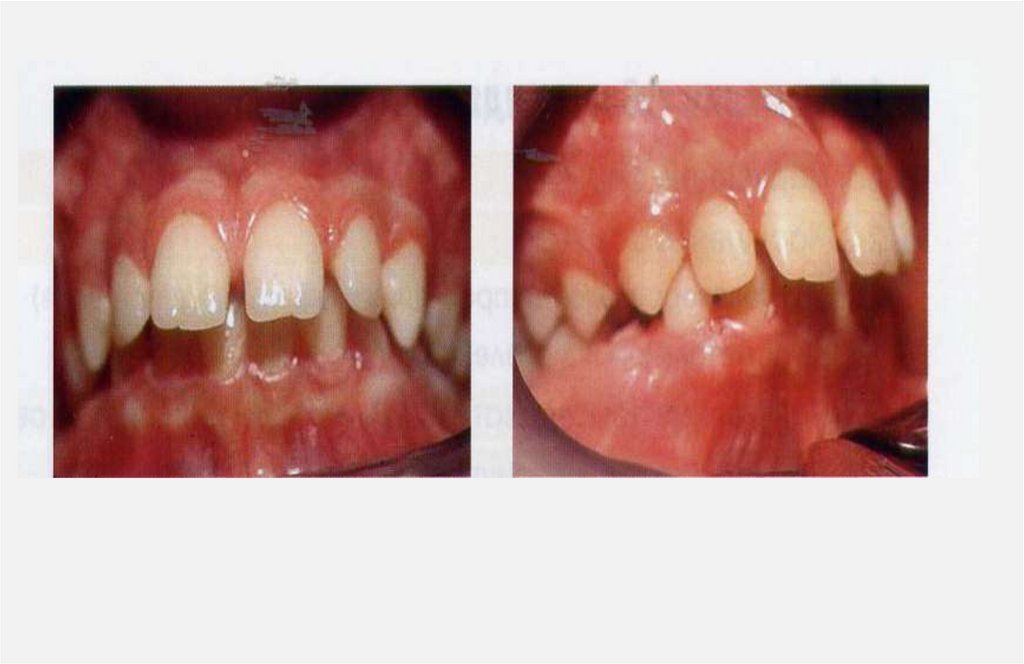

• Аномалии зубов и челюстей могут развиваться в результате заболеваний организма или быть

следствием врожденной патологии.

• Если морфологические нарушения появились под воздействием различных неблагоприятных

факторов после рождения ребенка, то их обозначают термином деформация.

Термин «деформация» (deformatio; лат. изменение формы) — более узкий по сравнению с

термином «аномалия» и обозначает изменение размеров и формы тела под действием

внешней силы.

Деформация является частным случаем аномалии.